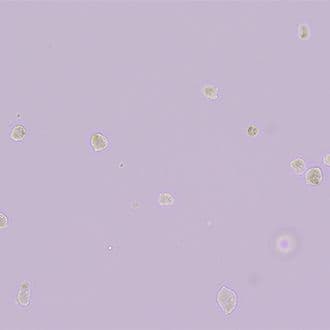

3. สภาพหลังจากการหยอดเซลล์

จะเห็นเซลล์ที่เรียงกันเป็นวงกลม